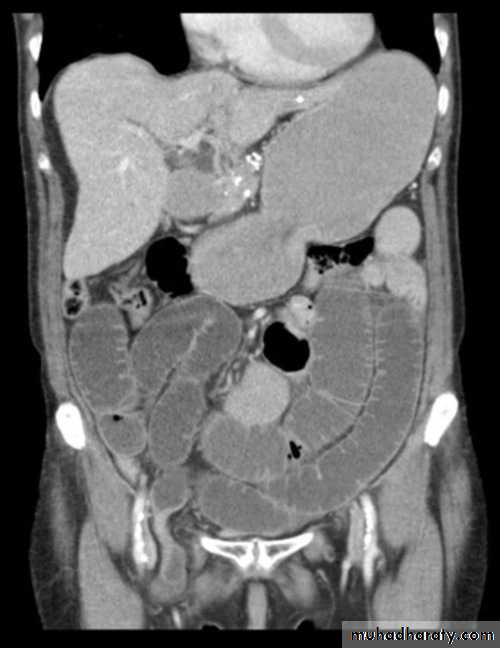

Obturator Hernia

9 : 1 female to male ratio

Typical patient is > 70 yrs of age

Multiparous women

Up to 20% bilateral

Concurrent Femoral hernias common

CLINICAL PRESENTATION

• Intestinal obstruction• most common presentation (80%)

• Up to 70% mortality with strangulation

• Overall mortality 25%

• Correct preoperative diagnosis in 20% to 38% of patients

ANATOMY

Formed by rami of the ischium and pubisBilaterally in anterolateral pelvic wall

Medial to the acetabulum

Obturator Foramen

• Covered by obturator membrane• Internal orifice closed by preperitoneal fat

• Contains obturator nerve and vessels

MRI

CT